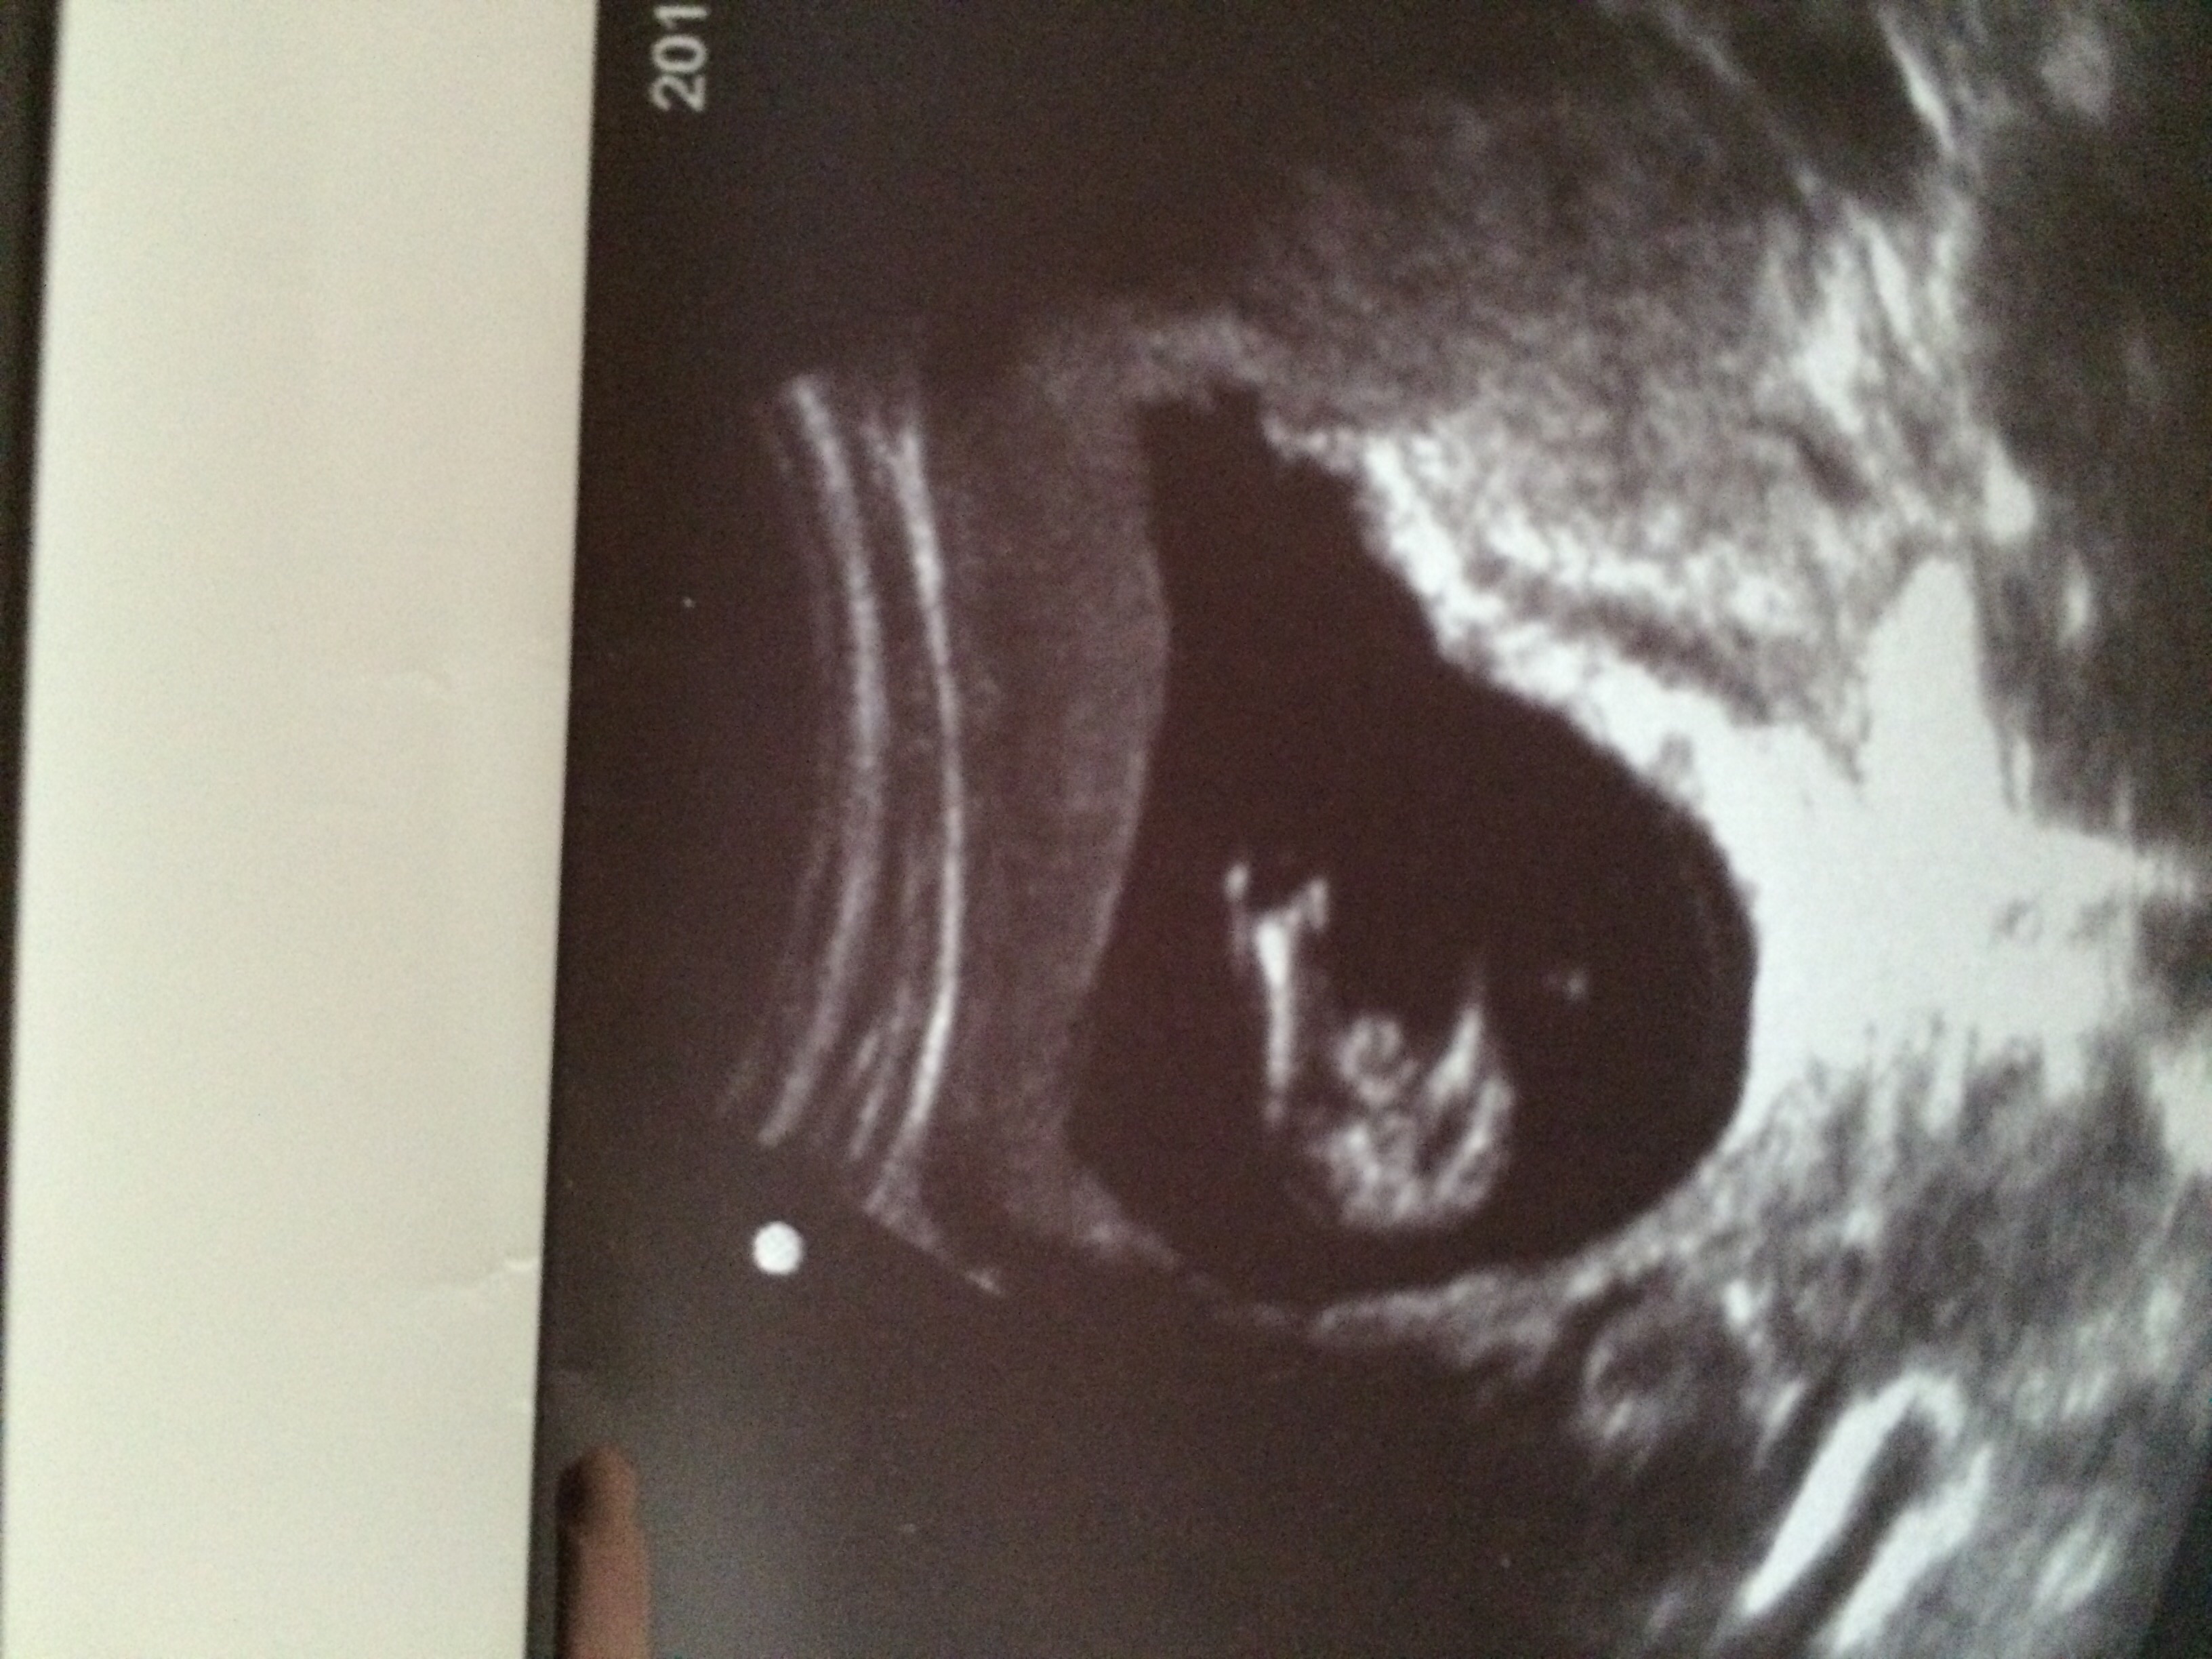

No but here's another of what I do have...Attachment 28448